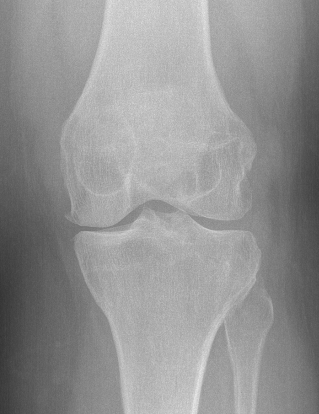

X-ray

Soft tissue swelling

Arthritic changes

Bone destruction

- invasion of adjacent metaphyseal cancellous bone

- may be suggestive of neoplasm

Bony involvement PVNS